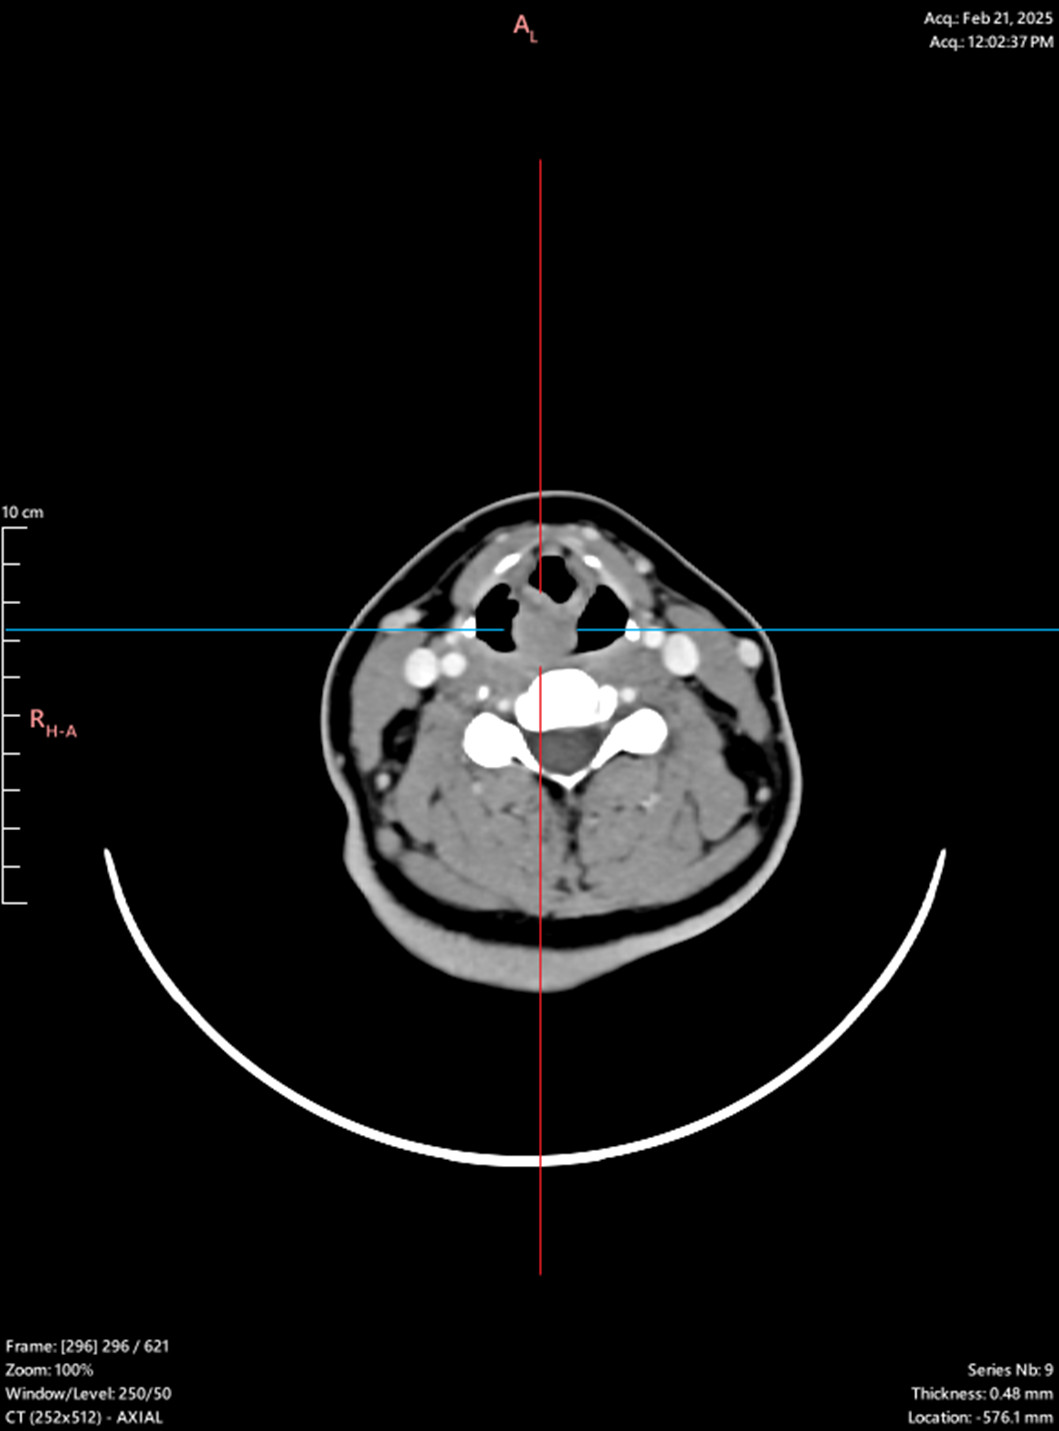

Laryngeal tumor - posterior commissure

Biopsy, granular cell tumor, granular cell myoblastoma, Abrikossoff tumor/div>

Symptoms: hoarseness, sensation of a foreign body in the throat, dysphagia